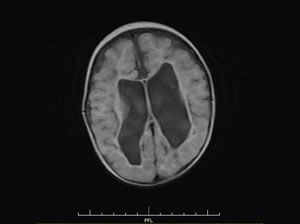

▲中央の黒い部分(脳室)の拡大と周囲にある白質の軟化

脳室周囲白質軟化症(PVL)とは、運動神経の集まる脳の「白質」の所が出生前に何らかの原因で血流が乏しかった(虚血状態)ことで、局所的に壊死となりその結果、上肢や下肢の麻痺が発生し運動障がいを起こす症状です。脳の発育が未熟な時期に生まれてしまう早産児(在胎32週以下)や低出生体重児(2,500g未満)で起こりやすく、脳性麻痺の原因となります。

未熟児(早産児あるいは低出生体重児)で出生するため、脳の中の脳室という部分の成長が乏しく周囲が軟らかい状態であり、身体から手足に向かう神経がダメージを受けている状態です。